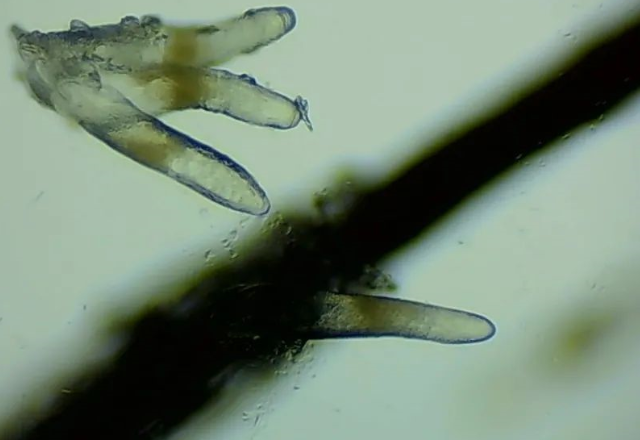

螨蟲檢查

▲顯微鏡下,睫毛上的螨蟲,它們長(zhǎng)著透明膠狀的身體,揮舞著爪子。